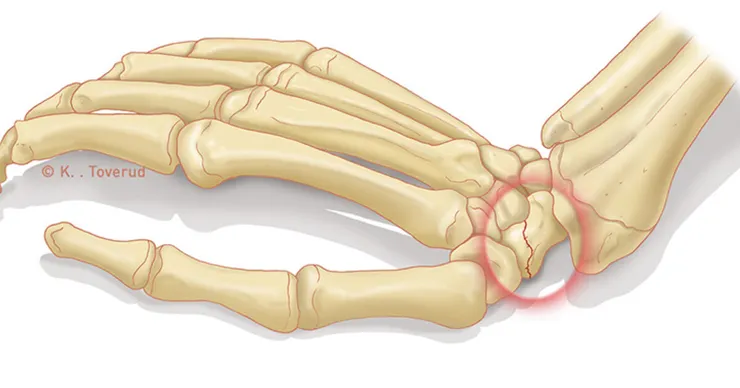

舟狀骨骨折( scaphoid fracture )

這也是手腕傷害最容易傷到的地方,而也因為是常動用到之地方,所以在癒合及復原也會比較久。久而久之會導致動力學跑掉、ROM、力量下降及腕關節退化